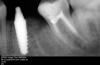

dantists Опубликовано 6 апреля, 2008 Поделиться Опубликовано 6 апреля, 2008 да однако проще купить нормальные ,чем извращаться .Нету у меня оксида алюминия .Я уже научился на своих .Неделю назад ставил наш родной отечественый имплант(ИОЛ) .Такое говно !!! ,скажу я вам !!! Отломил на втором витке.хорошо не в конце где нибудь,а то как раз вместо имплантации -операция по добыче импланта... Да купить то проще, а ради любопытства что не интерестно?Возьми одноэтапники implife если хочешь дёшево и сердито. 55$ штука. и микрорезьба и переменная высото витка., и фрезы лучше мисовских и альфовских, потому что конические. Я альфу ими ставлю. титан грейд4. Я в лунки удалённых ставлю даже без доработки, только колопаном допихиваю по бокам.Сверлю резве что пилотом по длине немножко.вот фото смотри. А если нету оксида алюминия. протрави 10 % плавиковой кислотой 3-4 раза, та что для протравки керамики, потом до белого отпескоструй обычным пескоструем внутриротовым.потом посмотришь на результат. Эндо не моё, говорю сразу. Ссылка на комментарий